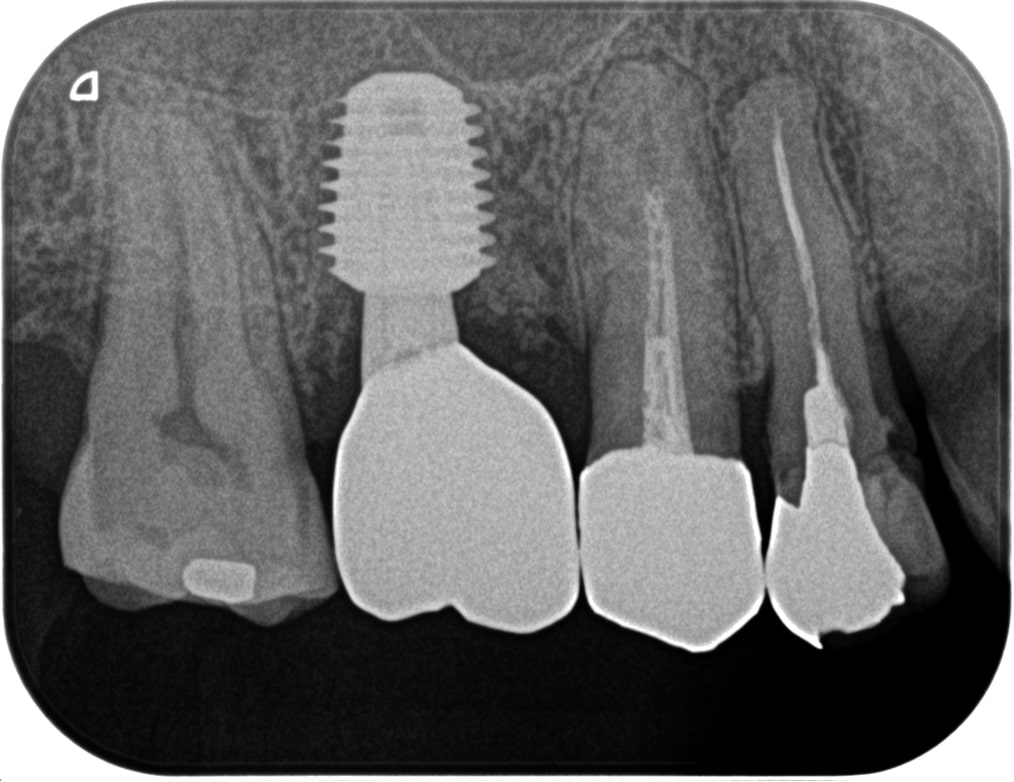

治療前

治療後

治療前

治療後

左下前・小臼歯部のブリッジによる荷重負担の為、隣在歯を守るインプラントを選択。

左下4番に単独インプラントを埋入。

オペ後、骨との密着値も良く、約2ヶ月後には、ジルコニアを装着し終了。

リスクとしては外科的侵襲がある。デメリットは、保険外診療の為、経済的負担がある。

費用 53万(税込)(オペ・仮歯・最終補綴物まで含む)